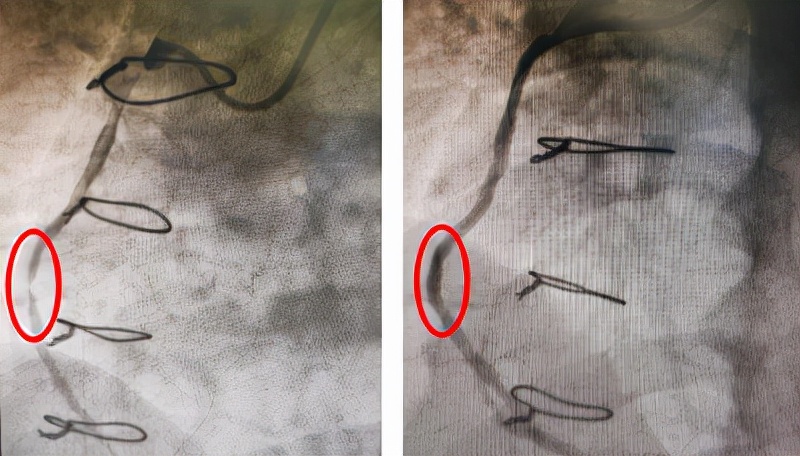

左冠静脉桥血管药物球囊治疗前后OCT影像对比

右冠静脉桥血管药物球囊治疗前后OCT影像对比